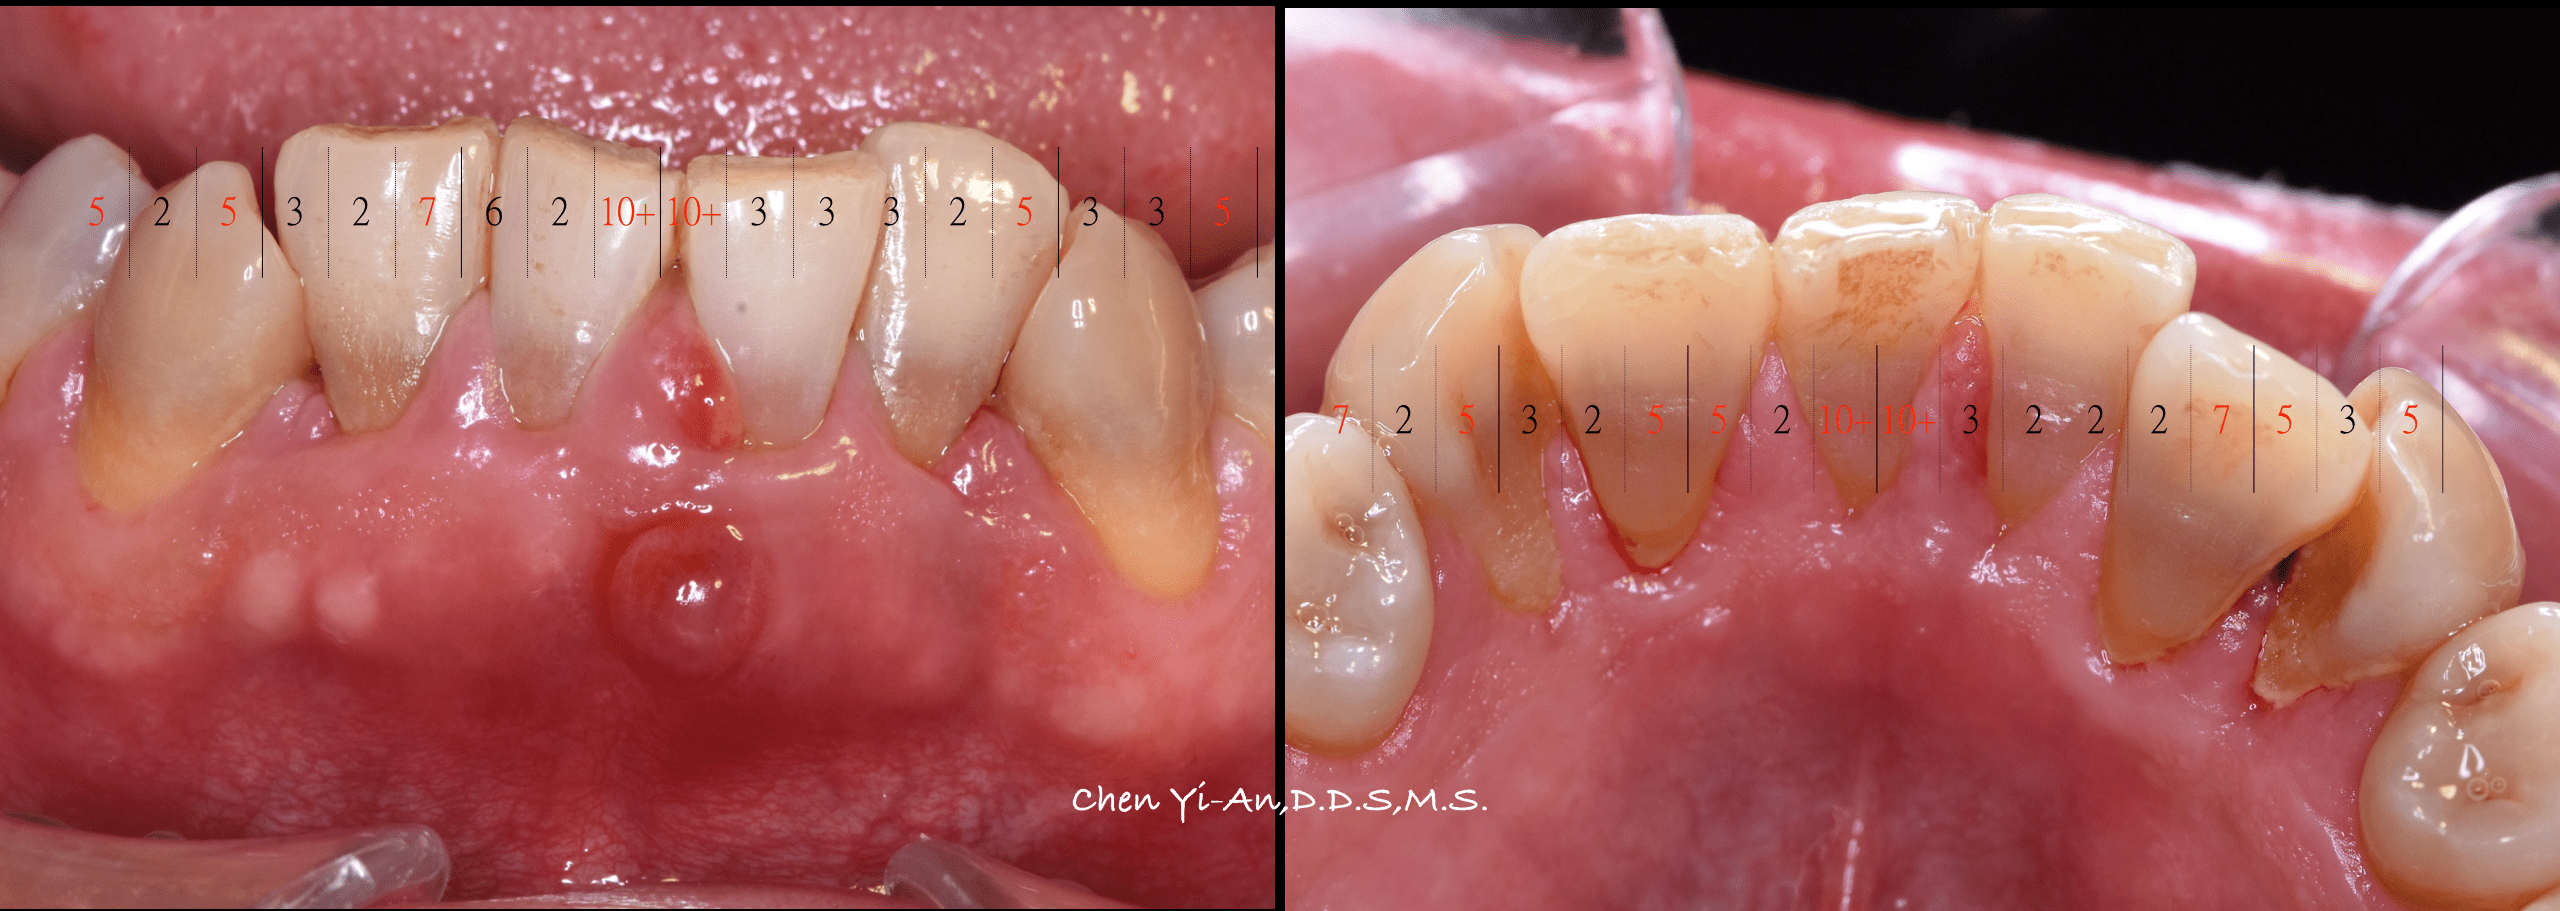

健康的牙齒跟牙齦幾乎是緊密貼合的。牙醫師會使用有刻度的牙周探針,針對每一顆牙齒進行探測檢查,沿著牙面弧度提放式行走,紀錄每一顆牙齒的牙周狀態。健康的牙周狀態,以探針探測,深度介於1-3mm之間,通常不會有滲血狀態出現,而是否有「探測時出血」,是牙齦健康的重要指標之一。當結石形成,發炎的現象越來越嚴重,患有牙周病的牙齒,探測深度會大於3mm,也就是進一步形成牙周囊袋,並且會逐漸加深。由於牙周病菌具有厭氧特性,氧氣較少的牙周囊袋正好成為孕育牙周病的溫床。牙周病菌不斷增生,散發出毒素,並且引發宿主免疫反應,造成齒槽骨吸收。當齒槽骨高度下降,便降低了對牙齒的支持力。如果置之不理、沒有妥善治療,經常導致牙齒喪失或需要拔除。

門診檢查一下,發現楊先生覺得不舒服的牙齒,已經是重度牙周病,骨頭被結石侵犯的範圍,已經侵蝕到牙根的分岔處。在傳統預後分析裡,這樣的牙齒預後落在『可疑』(Questionable)的範圍,決定要救或不救這顆牙齒,是門藝術。

但根據總分為11分的評分標準,這顆牙齒得到的分數是5分(牙齒能存活在嘴巴裡15年的機率是93%,能存活30年的機率也有80%),是可以積極治療的!